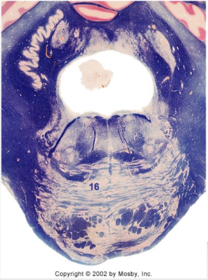

| Medullary pyramids | |

| Hypoglossal nucleus | |

| Hypoglossal nerve | |

| Dorsal motor nucleus of X | |

| Nucleus ambiguus | |

| Solitary tract | |

| Solitary nucleus | |

| ALS | |

| Medial lemniscus | |

| Medial longitudinal fasciculus | |

| Anterior spinocerebellar tract | |

| CN IX | |

| Inferior cerebellar peduncle | |

| Inferior olivary complex | |

| Dorsal cochlear nucleus | |

| Inferior vestibular nucleus | |

| Medial vestibular nucleus | |

| Spinal nucleus of V | |

| Spinal tract of V | |